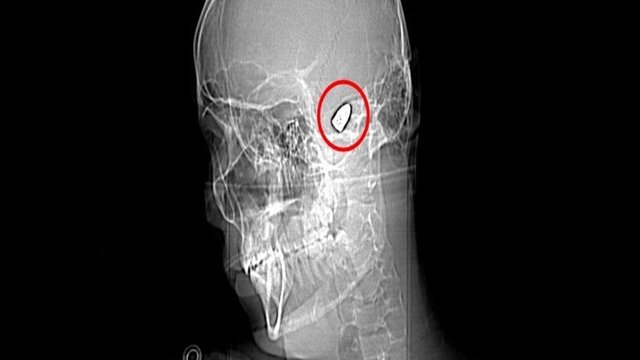

Şanlıurfa'nın Suruç ilçesinde 1 Haziran'da parkta bisiklet sürerken başına yorgun mermi isabet eden Sami Yusuf Kaya (6) ile 11 Haziran'da Antalya'nın Kepez ilçesinde evinin bahçesinde göğsüne yorgun mermi isabet eden Suriye uyruklu Abdurrahman Omar, hayatını kaybetti. Son olarak Adana'da 7 Haziran'da hobi bahçesinde karnına yorgun mermi isabet eden resim öğretmeni Burak Ateş (36) ile 9 Haziran'da sipariş hazırladığı sırada başına yorgun mermi isabet eden döner ustası Ramazan Malgir (39), yaralandı. ÇÜ Tıp Fakültesi Balcalı Hastanesi Acil Tıp Anabilim Dalı Başkanı Prof. Dr. Ahmet Sebe ve Adana Şehir Hastanesi Beyin ve Sinir Cerrahisi Bölümü'nden Doç. Dr. Ali İhsan Ökten, son dönemde çok sık gündeme gelen yorgun mermi vakalarıyla ilgili konuştu.

Prof. Dr. Ahmet Sebe özellikle yaz aylarında düğün mevsiminin de başlamasıyla birlikte bu vakaların hem çocuk hem yetişkin acilde sıklıkla görüldüğünü söyledi. Yılda yaklaşık 20-25 kişinin yorgun mermi kaynaklı acil servislerine başvurduğunu belirten Prof. Dr. Sebe, bu vakaların bazısının yapılan tetkiklerde tesadüfen tespit edilebildiğine dikkat çekti. Prof. Dr. Ahmet Sebe, "Bizim vatandaşlarımız silah sesi duyduğunda balkona, pencereye koşuyor. Bunun yerine gizlenmeyi, kendini korumaya çalışması gerekir. Silah sesi duyduğunuzda balkona, pencereye koşmayın; gizlenin. Çoğu zaman yorgun mermi fark edilmiyor, anlaşılmıyor. Tesadüf eseri bulduğumuz vakalar da oluyor. Kişi balkonda otururken bir bakıyorsunuz yere yığılmış. Sanki bir inme ya da beyin kanaması geçirmiş gibi görünüyor. Ancak hastaneye geldiğinde çekilen görüntülemelerde bunlar ortaya çıkıyor. Yorgun mermi kol ve bacak gibi uzuvlara geldiğinde hastaneye ulaşmalarında genellikle bir sıkıntı olmuyor ancak beyin, kalp ya da karın içindeki bir organa geldiğinde hastalar acile ulaşamadan hayatını kaybedebiliyor. İlk yardım uygulaması olarak bası yapılabilir ama iç organlara geldiyse kişinin yapacağı en doğru şey, 112 Acil Çağrı Merkezi'ne haber verip bir an önce hastayı sağlık kuruluşuna ulaştırmaktır. Buraya ulaştığında ise hastanın durumuna göre beyin cerrahi, göğüs cerrahi, genel cerrahi ya da girişimsel radyolojiye yönlendirerek, tedavisini gerçekleştiriyoruz" diye konuştu.

Doç. Dr. Ali İhsan Ökten de "Yorgun mermi, beynin sessiz bölgelerine geldiğinde çok fazla hasar yaratmayabilir. Ancak beynin derin bölgelerine doğru gittikçe orada damar yapıları da yoğun olduğu için beyin kanamalarına yol açıp ciddi sakatlanmalara, felç gibi durumlara ve hatta bazı vakalarda ölümcül sonuçlara neden olur. Bu vakalarda geçen yıllara oranla göreceli olarak bir artış olduğunu söyleyebilirim. Özellikle bireysel silahlanma oranının giderek artması, düğün, nişan, şenlik, festival, maç sonrasında veya asker uğurlamalarında bilinçsizce ateş açarak, sözde kutlama yapılması bu oranların artmasına sebep oluyor. Burada önemli olan tüm bunları denetlemek, kişisel silahlanmayı önlemek ya da cezaların artırılması yoluna gidilmesinin önleyici olacağını düşünüyorum" dedi.